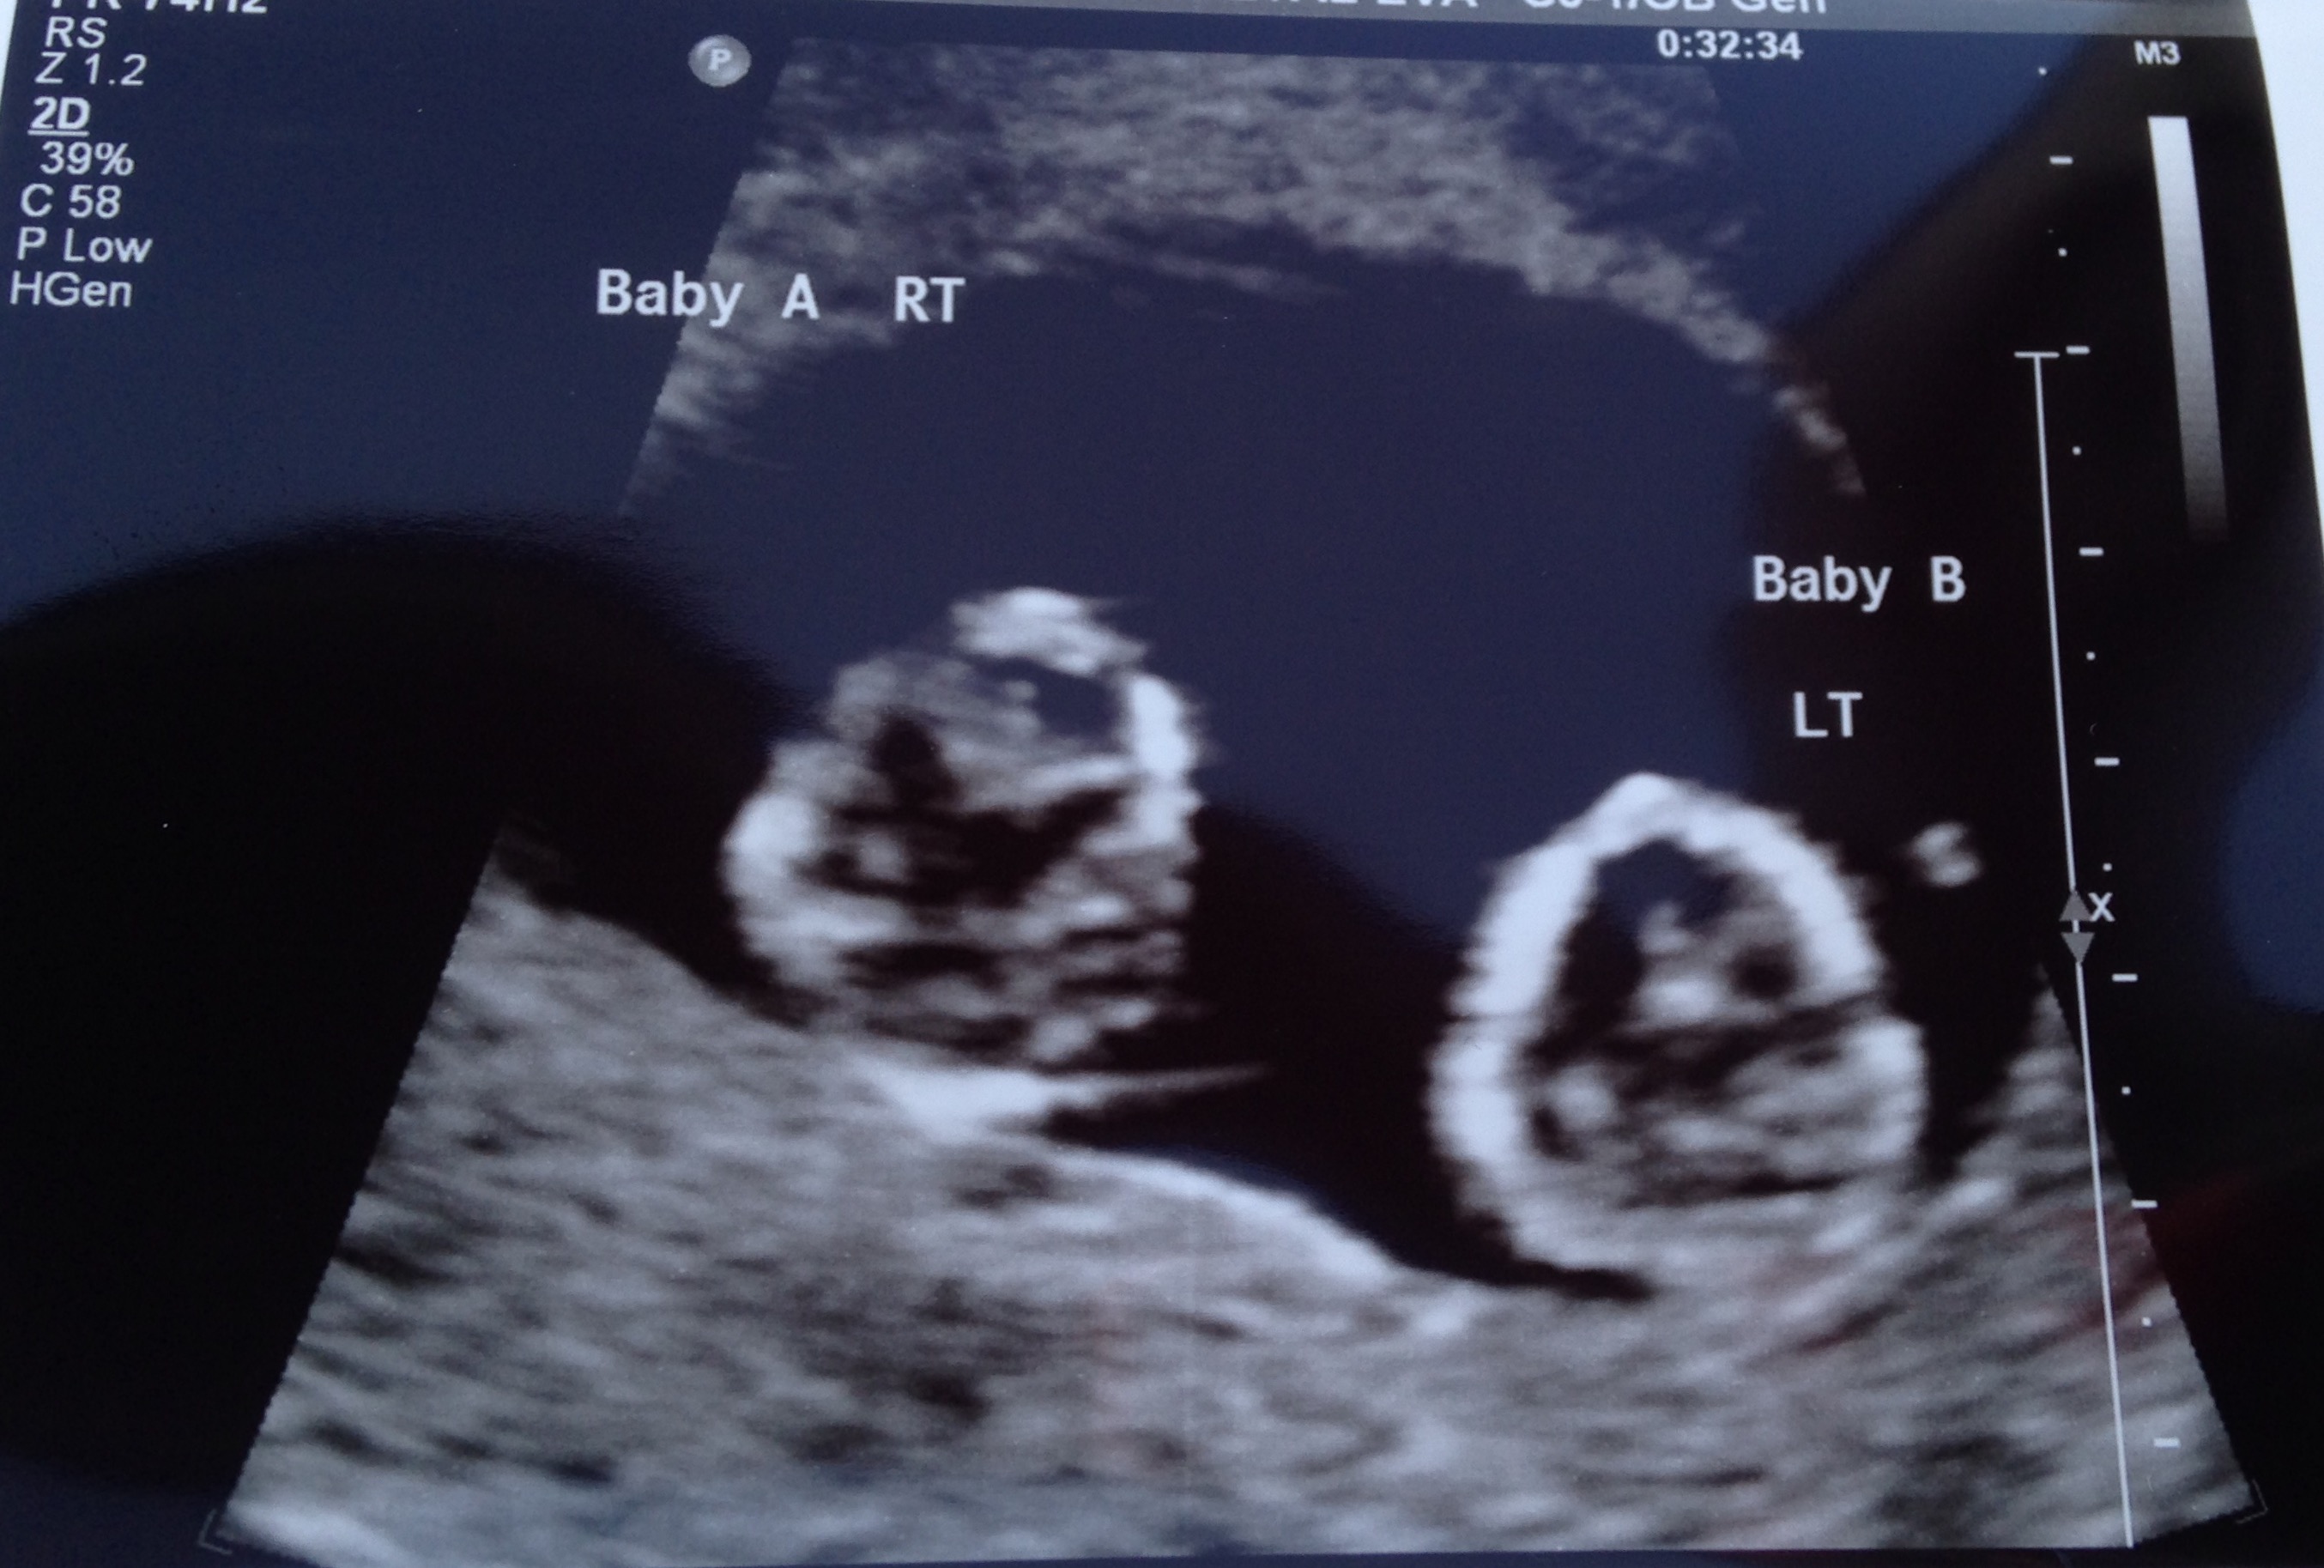

Twins!!!!!! I had two ultrasounds, one week apart.

I'm having twins too!! How far along are you?